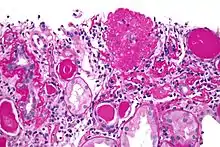

![]() | |

| Light micrograph of focal segmental glomerulosclerosis, hilar variant. Kidney biopsy. PAS stain. | |

The individual components of the name refer to the appearance of the kidney tissue on biopsy: focal—only some of the glomeruli are involved (as opposed to diffuse), segmental—only part of each glomerulus is involved (as opposed to global),[19] glomerulosclerosis—refers to scarring of the glomerulus (a part of the nephron (the functional unit of the kidney)). The glomerulosclerosis is usually indicated by heavy PAS staining and findings of immunoglobulin M (IgM) and C3-convertase (C3) in the sclerotic segment.[20]